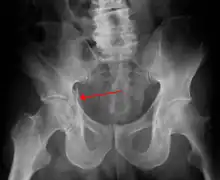

| Acetabular fracture | |

| Acetabular fracture as seen on plain X-ray |

Fractures of the acetabulum occur when the head of the femur is driven into the pelvis. This injury is caused by a blow to either the side or front of the knee and often occurs as a dashboard injury accompanied by a fracture of the femur.[1]